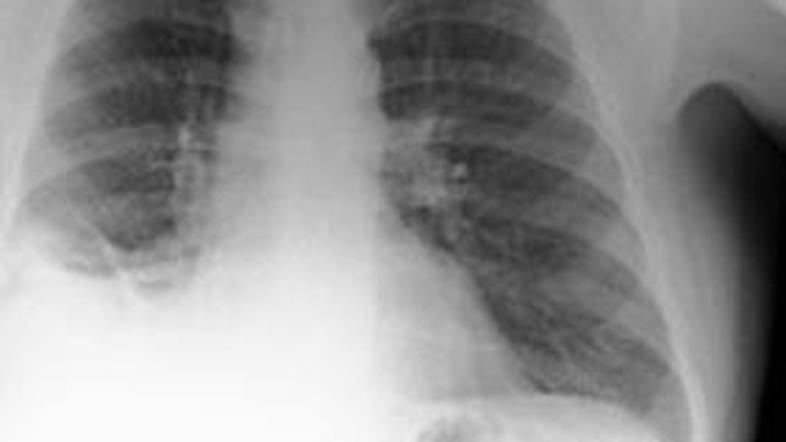

Rentgenska preiskava je pokazala na veliko senco v pljučih.

Rentgenska preiskava je pokazala na veliko senco v pljučih, po temeljitem pregledu pa so zdravniki ugotovili, da ima moški v pljučih stožec. Šlo je pravzaprav za igračo oziroma prometni stožec iz kompleta igrač znanega proizvajalca igrač Playmobil. Moški se je pozneje spomnil, da je to igračo dobil kot darilo za svoj sedmi rojstni dan.

Celih 40 let je imel v pljučih tujek. Članek, objavljen v znastveni reviji IBM navaja, da je moški zdravnikom dejal, da se je v mladosti "pogosto in zelo rad igral s temi igračami in kakšno tudi vdihnil."